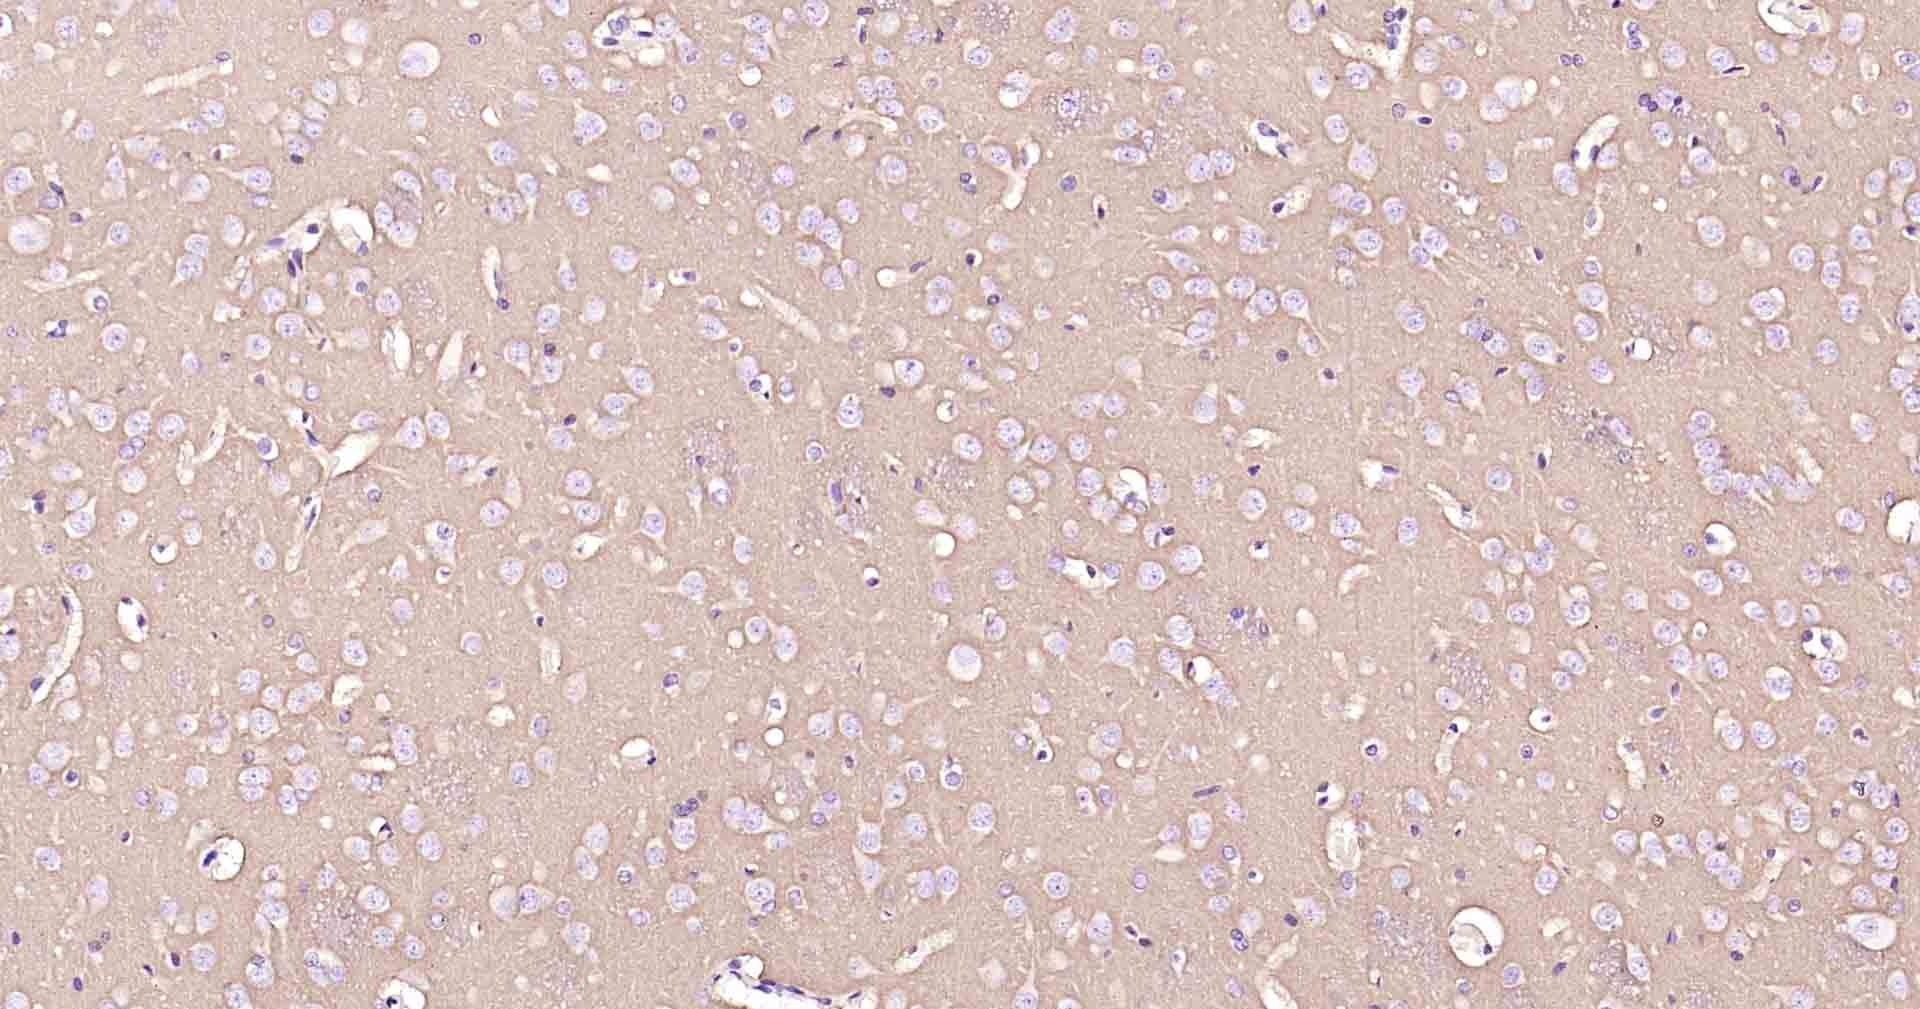

Paraformaldehyde-fixed, paraffin embedded Human Cerebrum; Antigen retrieval by boiling in sodium citrate buffer (pH6.0) for 15 min; Antibody incubation with ATP1B1 Monoclonal Antibody, Unconjugated(bsm-61065R) at 1:100 overnight at 4°C, followed by conjugation to the SP Kit (Rabbit, SP-0023) and DAB (C-0010) staining.

Paraformaldehyde-fixed, paraffin embedded Rat Cerebrum; Antigen retrieval by boiling in sodium citrate buffer (pH6.0) for 15 min; Antibody incubation with ATP1B1 Monoclonal Antibody, Unconjugated(bsm-61065R) at 1:100 overnight at 4°C, followed by conjugation to the SP Kit (Rabbit, SP-0023) and DAB (C-0010) staining.

Paraformaldehyde-fixed, paraffin embedded Mouse Cerebrum; Antigen retrieval by boiling in sodium citrate buffer (pH6.0) for 15 min; Antibody incubation with ATP1B1 Monoclonal Antibody, Unconjugated(bsm-61065R) at 1:100 overnight at 4°C, followed by conjugation to the SP Kit (Rabbit, SP-0023) and DAB (C-0010) staining.